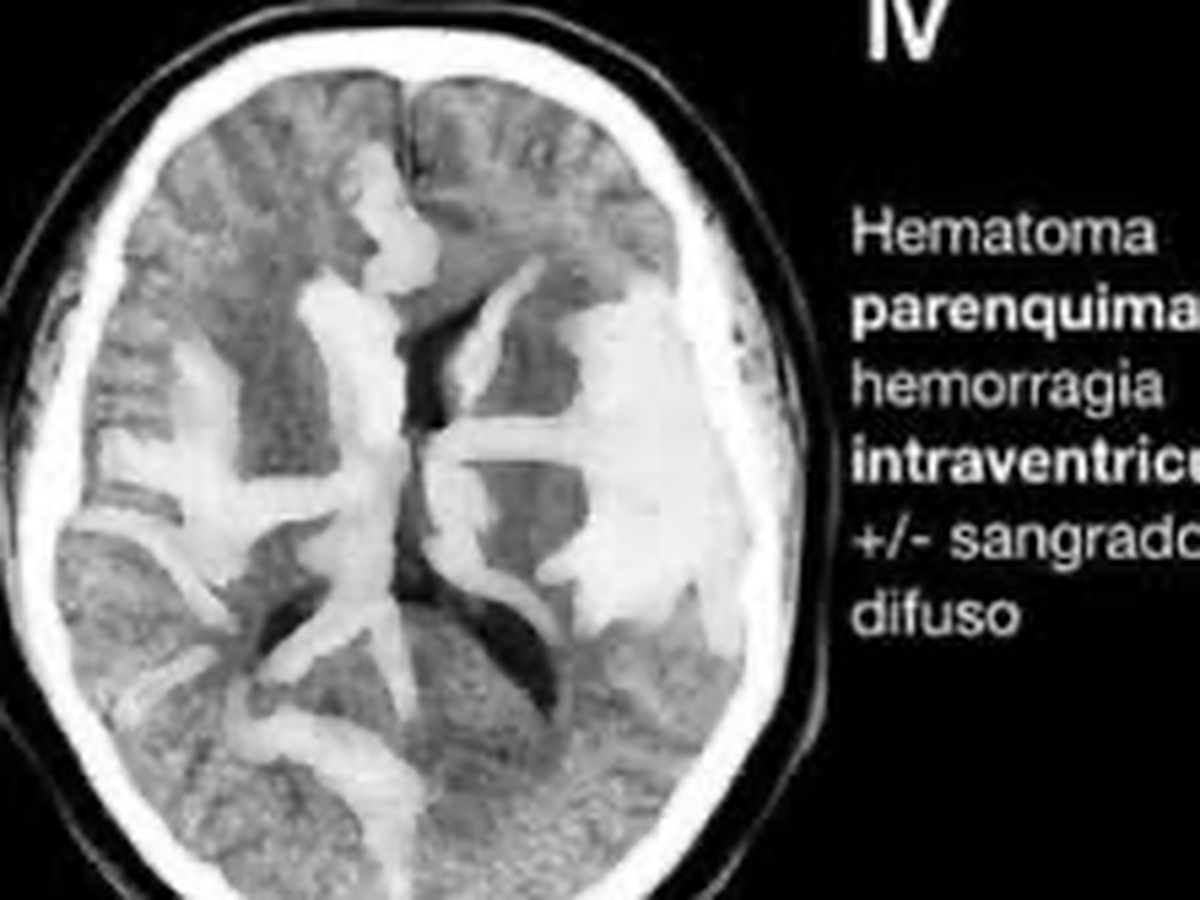

Hola, Me llamo Gus y mi mamá sufrió de una hemorragia cerebral fisher IV a raíz de una ruptura de un aneurisma cerebral, por lo que solicito su ayuda para alcanzar a cubrir los gastos que de esto conlleva.